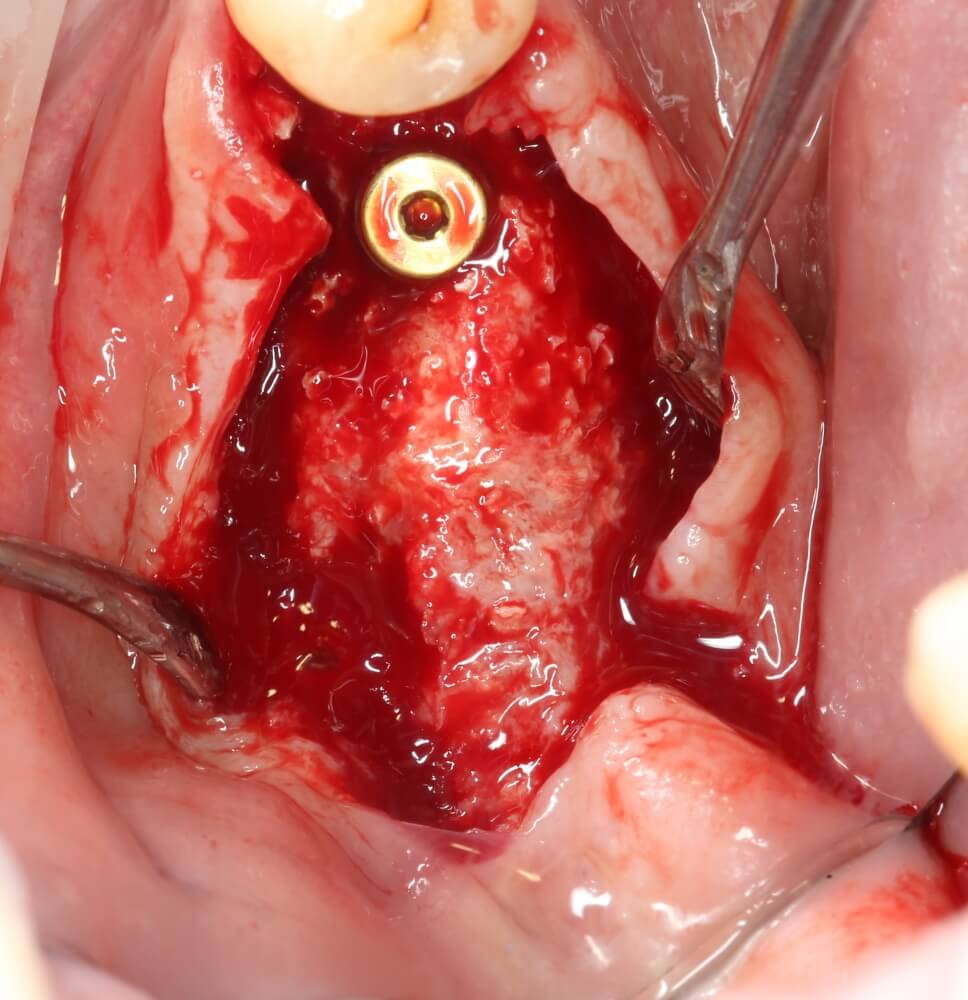

Изоляция области аутографта и имплантатов барьерной мембраной.

Конкретно в этом клиническом случае между костным аутотрансплантатом, ложем и имплантатами есть пустое пространство. Если его не изолировать от мягких тканей, они прорастут и осложнят интеграцию аутографта. Поэтому я решил перекрыть костный блок барьерной мембраной, пусть это делает хирургическую операцию немного дороже.

— я использовал барьерную мембрану Geistlich Bio-Gide, которая имеет две разные поверхности: с одной стороны она рыхлая «адгезивная», с другой — гладкая и прочная. Как укладывать — на результат не влияет, но в плане удобства рыхлую поверхность мы «приклеиваем» к тому, на чем требуется барьерную мембрану удержать. В данном случае хотелось бы удержать её на костной поверхности — следовательно, мы укладываем её рыхлой поверхностью к кости.

— много лет мы используем антибиотики для интраоперационной профилактики инфекционно-воспалительных осложнений. Уже в то время мы пришли к выводу, что удобнее всего — порошки антибактериальных препаратов для приготовления раствором: дешевые, стерильные, в удобной упаковке. Прямо в виде порошка их можно добавлять в графт, растворы для ирригации, либо использовать так, как показано на фото. Еще мы используем порошок антибиотика для изготовления пасты, которой обрабатываем имплантаты в процессе ревизии или при лечении периимплантита. Это удобнее и эффективнее, чем интраоперационное использование жидких форм антибактериальных препаратов.

— ты знаешь, что барьерная мембрана может выполнять две функции, каркасную и изолирующую. Первая функция требует обязательной фиксации и натяжения, вторая — нет. В нашем случае «каркасом» регенерата является костный блок, а барьерная мембрана нужна только для изоляции. Поэтому она не требует натяжения и фиксации пинами.

После я внимательно проверил, что костный блок и имплантаты полностью перекрыты. Теперь рану можно ушивать.